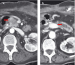

Chronische Pankreatitis - seltene Komplikationen: von chronisch-onkologisch bis zur akuten Hämorrhagie Journal für Gastroenterologische und Hepatologische Erkrankungen 2007; 5 (4): 13-21 Volltext (PDF) Summary Abbildungen Keywords: Chirurgie, chronische Pankreatitis, Gastroenterologie, Pankreas, Radiologie Die chronische Pankreatitis ist durch eine große Bandbreite von Ursachen, klinischen Ausprägungsgraden und morphologischen Erscheinungsformen gekennzeichnet. Durch adäquate konservative Behandlung lassen sich Verläufe über Jahre symptomarm oder -frei beherrschen. Standardisierte Operationen haben sich durch Minimierung operativer und postoperativer Risiken zur Beseitigung von Gangabflußstörungen und Schmerzen zunehmend etabliert. Nach wie vor bestehen aber die besonderen Herausforderungen an Diagnostik und Therapie darin, die Pankreatitis gegen andere Krankheitsbilder, insbesondere das Pankreaskarzinom, abzugrenzen und bei den oft lange konstanten Verläufen akute Komplikationen zu erkennen und zu behandeln. Diese Schwierigkeiten werden in der Übersicht dargestellt, wobei die aus der Literatur gewonnenen Behandlungsmaximen zur Verdeutlichung der Relevanz für die Klinik konkret an zwei Patientenverläufen diskutiert werden: Zunächst stellt sich bei einer 63jährigen Patientin mit Alkohol- und Nikotinabusus, Hyperlipidämie, Pancreas divisum und einer über 2 Jahre unterschiedlich floriden, z.T. nekrotisierenden Pankreatitis mit konsekutiver Pseudozystenausbildung als Ursache der Pankreasgangabflußstörung ein Pankreaskopfkarzinom heraus, das mittels partieller Duodenopankreatektomie nach Whipple behandelt wurde. Beim zweiten, 47jährigen Patienten mit chronischer, ethyltoxischer Pankreatitis mit Arrosionsblutung eines Pseudoaneurysmas der Milzarterie und Milzruptur bei hämorrhagischem Milzinfarkt bei Milzvenenverschluß wird ersichtlich, wie sich ein scheinbar stabiler Verlauf akut dramatisch entwickeln kann. |